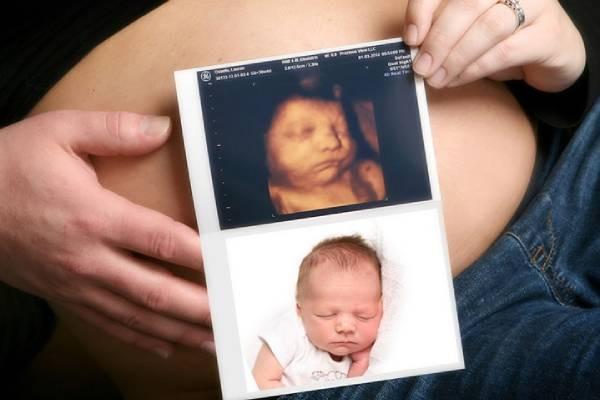

The cycling community erupted in emotion after golden couple Julian Alaphilippe and Marion Rousse revealed they are expecting their third child. The announcement came with an adorable ultrasound photo that went viral instantly, amassing over 500,000 likes within two hours.

Now, as Marion enters her second trimester, Julian has reportedly scaled back his training schedule to spend more time with his family. “For once,” he said, laughing, “I’m happy to lose to love.”